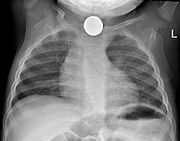

Prior to undertaking endoscopy, attempts should be made to locate the foreign body with x-rays or other non-invasive techniques. For radio-opaque objects, x-rays of the neck, chest and abdomen can be used to locate the foreign body and assist endoscopy. Alternative approaches, including the use of metal detectors, have also been described.

X-rays are also useful for identifying the type of foreign body ingested and complications of foreign body ingestion, including mediastinitis and perforation of the esophagus.